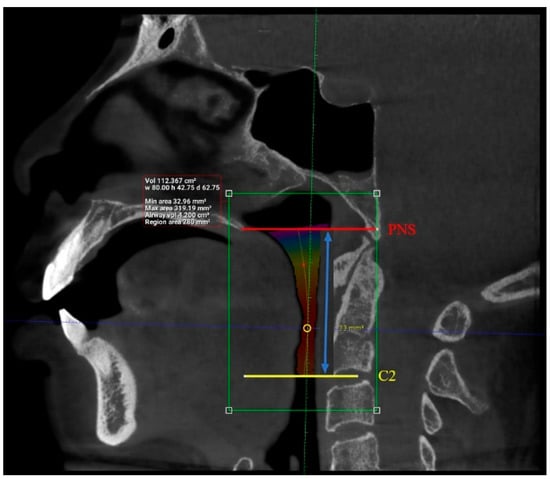

| Length (mm) | 101 | 29.93 | 55.75 | 42.63 | 6.24 |

| Total volume (cm3) | 101 | 94.58 | 173.45 | 131.67 | 17.91 |

| Average volume (cm3) | 101 | 3.34 | 32.09 | 11.10 | 5.21 |

| Antero-posterior (mm) | 101 | 1.00 | 14.50 | 6.44 | 3.19 |

| Width (mm) | 101 | 8.00 | 37.00 | 21.69 | 6.54 |